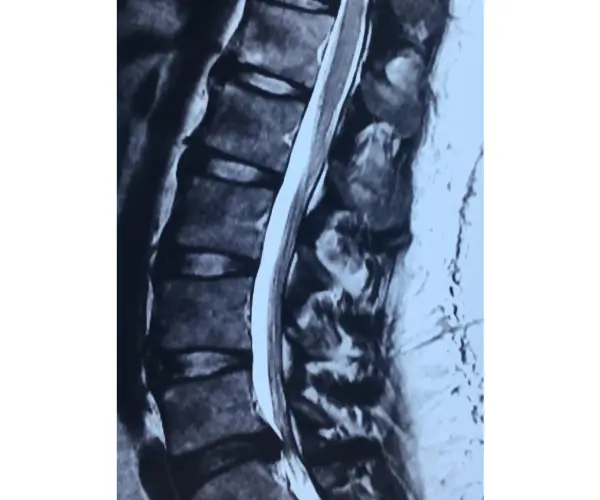

MRI disc lumbar

Lumbar Disc Prolapse